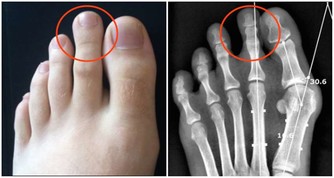

▼請大家先回想自己坐在馬桶時的情形,是不是膝蓋和身體保持大約90度的姿勢呢?以坐姿排便時,幫助控便的恥骨直腸肌因為姿勢的問題無法放鬆,從而導致了如廁時的困難;相反地,若是以身體和膝蓋呈現110度的蹲姿排便時,恥骨直腸肌才能完全疏鬆,在一定程度的腹壓幫助下,糞便就能更輕易地從體內排出。